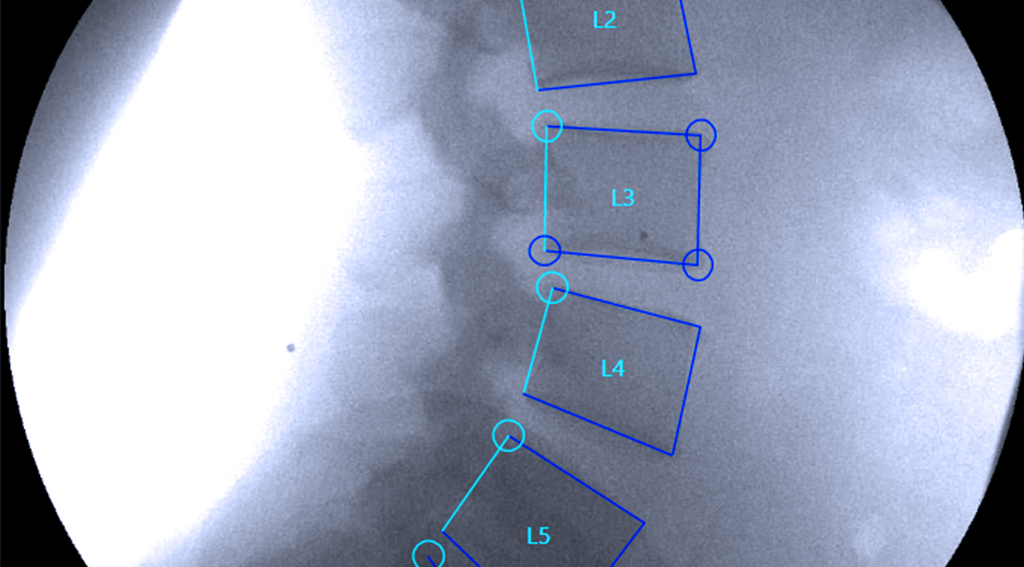

Vertebral Motion Analysis, or VMA®, is an FDA-cleared motion-based spine diagnostic that shows how the spine behaves in real time. Instead of taking still pictures like standard X-rays or MRIs, VMA captures continuous imaging as the patient gently bends forward, backward, and side to side.

Using a surgical-grade C-arm and proprietary software, VMA measures the movement of each vertebra with sub-millimeter accuracy. This reveals spinal ligament injuries and mechanical instability that are invisible on imaging at rest.

A surgical C-arm takes continuous images at eight frames per second throughout the bending cycle.

Quantitative Motion Analysis

Specialized software tracks and measures:

- Vertebral translation (sliding)

- Angular rotation

- Excessive motion patterns

- Segmental instability

- Motion asymmetry

- Abnormal load distribution

- Measurements are accurate within 0.5–0.7 mm, far beyond the sensitivity of standard imaging.